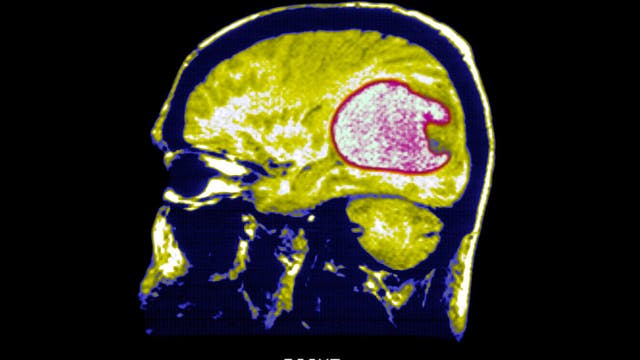

Scientists use new strategy to successfully shrink tumors in early brain cancer trials

Researchers converted immune cells from patients into "living drugs" with the ability to recognize and combat glioblastoma, a form of brain cancer.